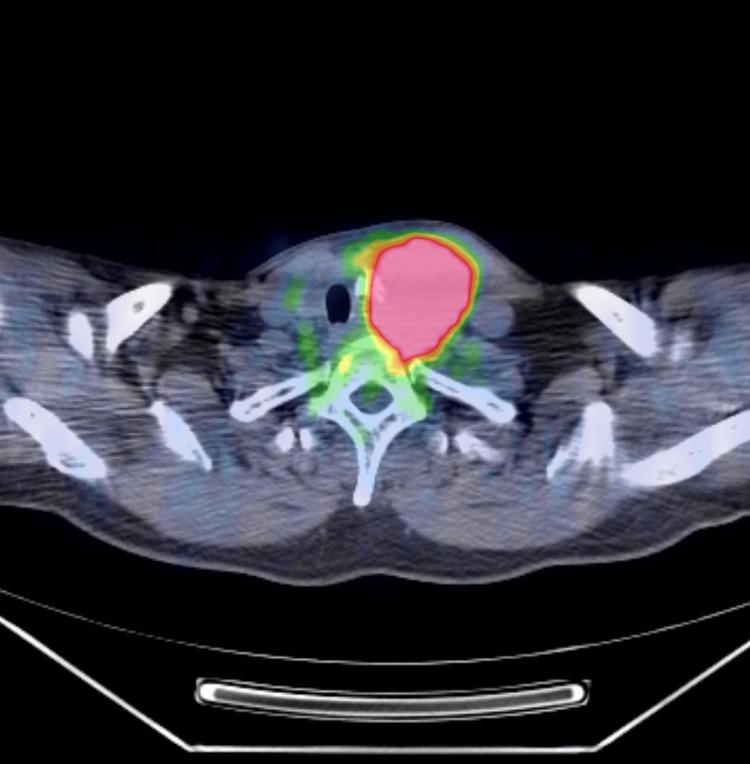

Anaplastic thyroid carcinoma, a rare type of primary thyroid cancer, is one of the most aggressive neoplasms with a poor prognosis. Many cases are in the advanced stage at the time of the initial visit, and curative treatment is impossible. Because of the highly radioresistant nature of anaplastic thyroid carcinoma, this condition cannot be properly controlled with conventional radiotherapy. Herein, we report the case of a patient with anaplastic thyroid carcinoma who underwent hypofractionated radiotherapy, attained a complete response, and is still alive more than 10 years after treatment with no evidence of disease. To overcome the high radioresistance of anaplastic thyroid carcinoma, we administered 50 Gy in 10 fractions three times a week. Furthermore, we administered paclitaxel and carboplatin sequentially before and after radiotherapy. Consequently, the patient completed treatment and reached a complete response. He is still alive more than 10 years after treatment with no evidence of disease or severe adverse events. Hypofractionated radiation therapy may provide good control of locally advanced anaplastic thyroid carcinoma.

间变性甲状腺癌是一种罕见的原发性甲状腺癌,是最具侵袭性的肿瘤之一,预后较差。许多病例在初诊时就已处于晚期,无法进行根治性治疗。由于间变性甲状腺癌具有高度放射抗性,传统放疗无法有效控制这种疾病。在此,我们报告一例间变性甲状腺癌患者,该患者接受了大分割放疗,获得了完全缓解,并且在治疗后存活超过10年,无疾病迹象。为克服间变性甲状腺癌的高放射抗性,我们每周三次,分10次给予50 Gy的剂量。此外,我们在放疗前后序贯给予紫杉醇和卡铂。结果,患者完成治疗并达到完全缓解。治疗后他存活超过10年,无疾病迹象或严重不良事件。大分割放射治疗可能对局部晚期间变性甲状腺癌有良好的控制效果。